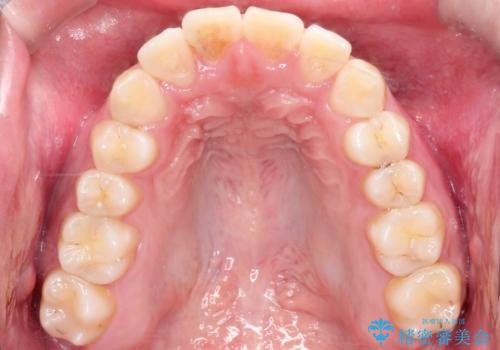

【ワイヤー矯正】前歯の凸凹を治したい。

- 前歯の凸凹を主訴に来院されました。

患者様がマウスピース矯正の使用時間に不安があるため、ワイヤー矯正にて治療を行なっております。